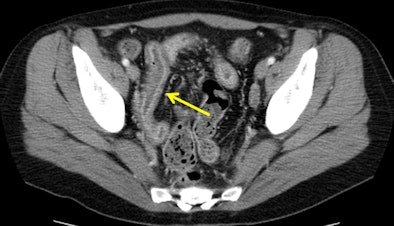

![]() |

| Images show patient with terminal ileitis. CT (above) and gadolinium-enhanced MR enterography (below) show abnormal wall thickening. Both readers agreed on the interpretation of images. All images courtesy of David Grand, MD. |